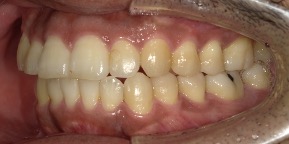

33歳女性のビフォーアフター

| 診断 | 空隙 |

| 治療方針 | 治療方針:前歯の咬合関係改善と空隙閉鎖を主な目的にて主にIPR(歯と歯の間をわずかに削合してスペースを獲得する方法)を組み込んだ動的矯正治療を行い、空隙、前歯咬合を改善後、保定を行う。臼歯部の咬合関係はプランの都合上維持することとした。 |

| 治療費 ※ | 67万8千円(診断、型取り、矯正中のメンテナンス、保定装置を含む料金) |

| 治療期間 | 6か月 |

| リスク | 1日20時間以上マウスピースを使用できない場合、歯が動かなかったり、想定しない誤差により不完全に終わる可能性がある。装着時や食事時に痛みを伴う。歯肉退縮や虫歯になるおそれがある。また、指導通りに装着できていない場合や適切なブラッシングが出来ていないとそのリスクが高くなる。歯根が短くなることがある。ごくまれに歯の神経が損傷してしまうことがある。過去にぶつけたり深い虫歯治療をしたことがあるとそのリスクはやや高くなる。矯正後には保定装置が必要。適切な使用ができない場合、後戻りの原因となる。将来的に歯並びが動いて再矯正が必要な場合がある。親知らずが正常に生えていない場合、その可能性がやや高くなる。 |